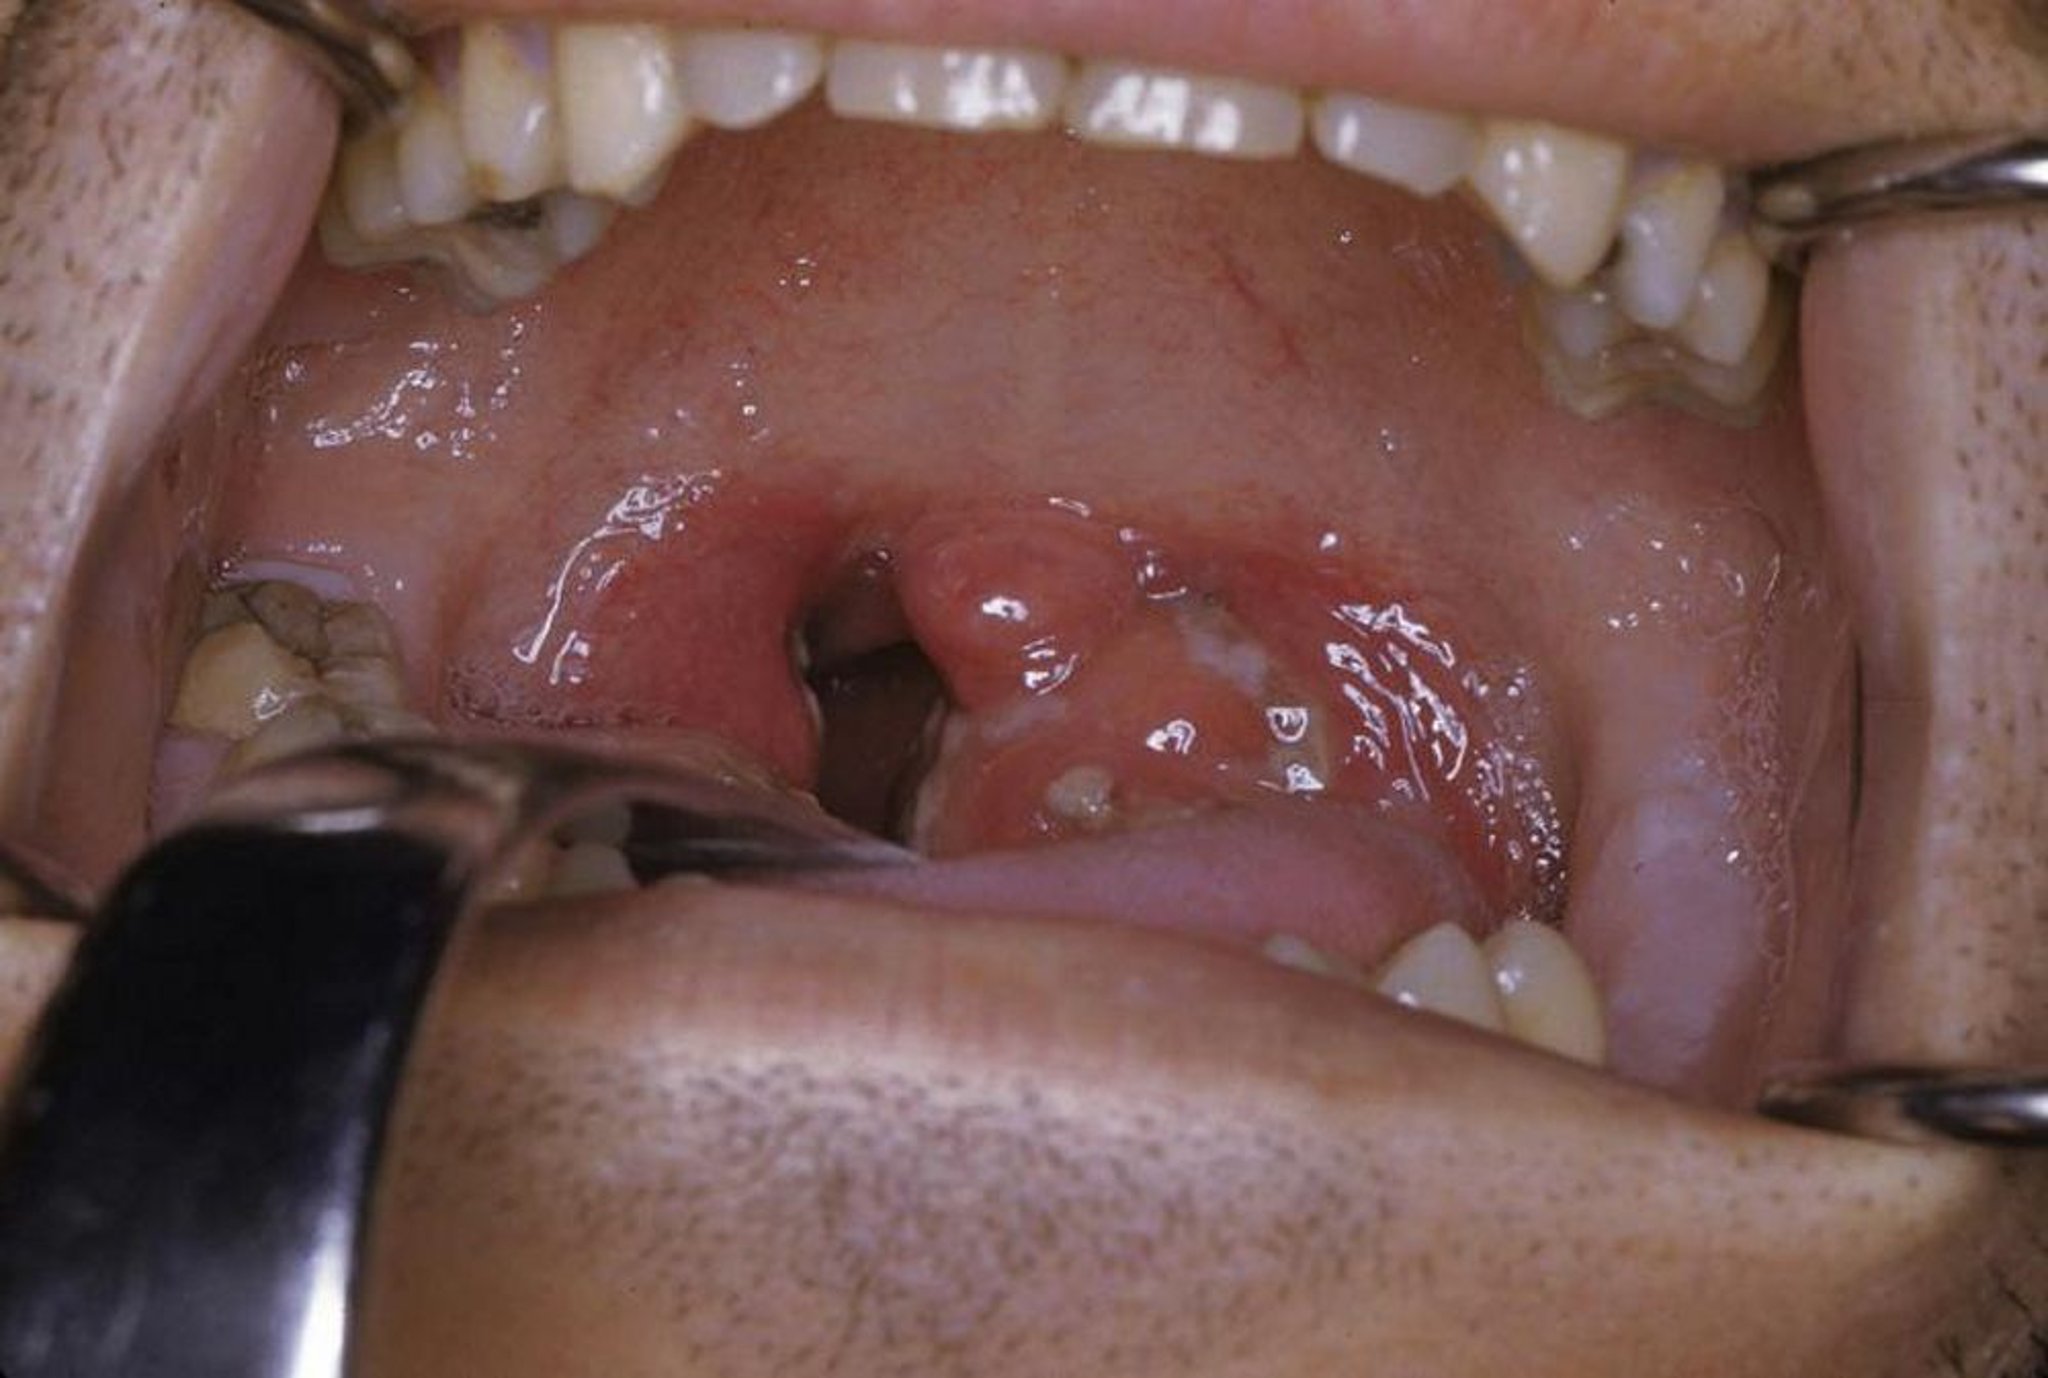

Amigdalite aguda

Esta foto mostra amigdalite aguda com exsudato e eritema.

Foto fornecida por Clarence T. Sasaki, MD.